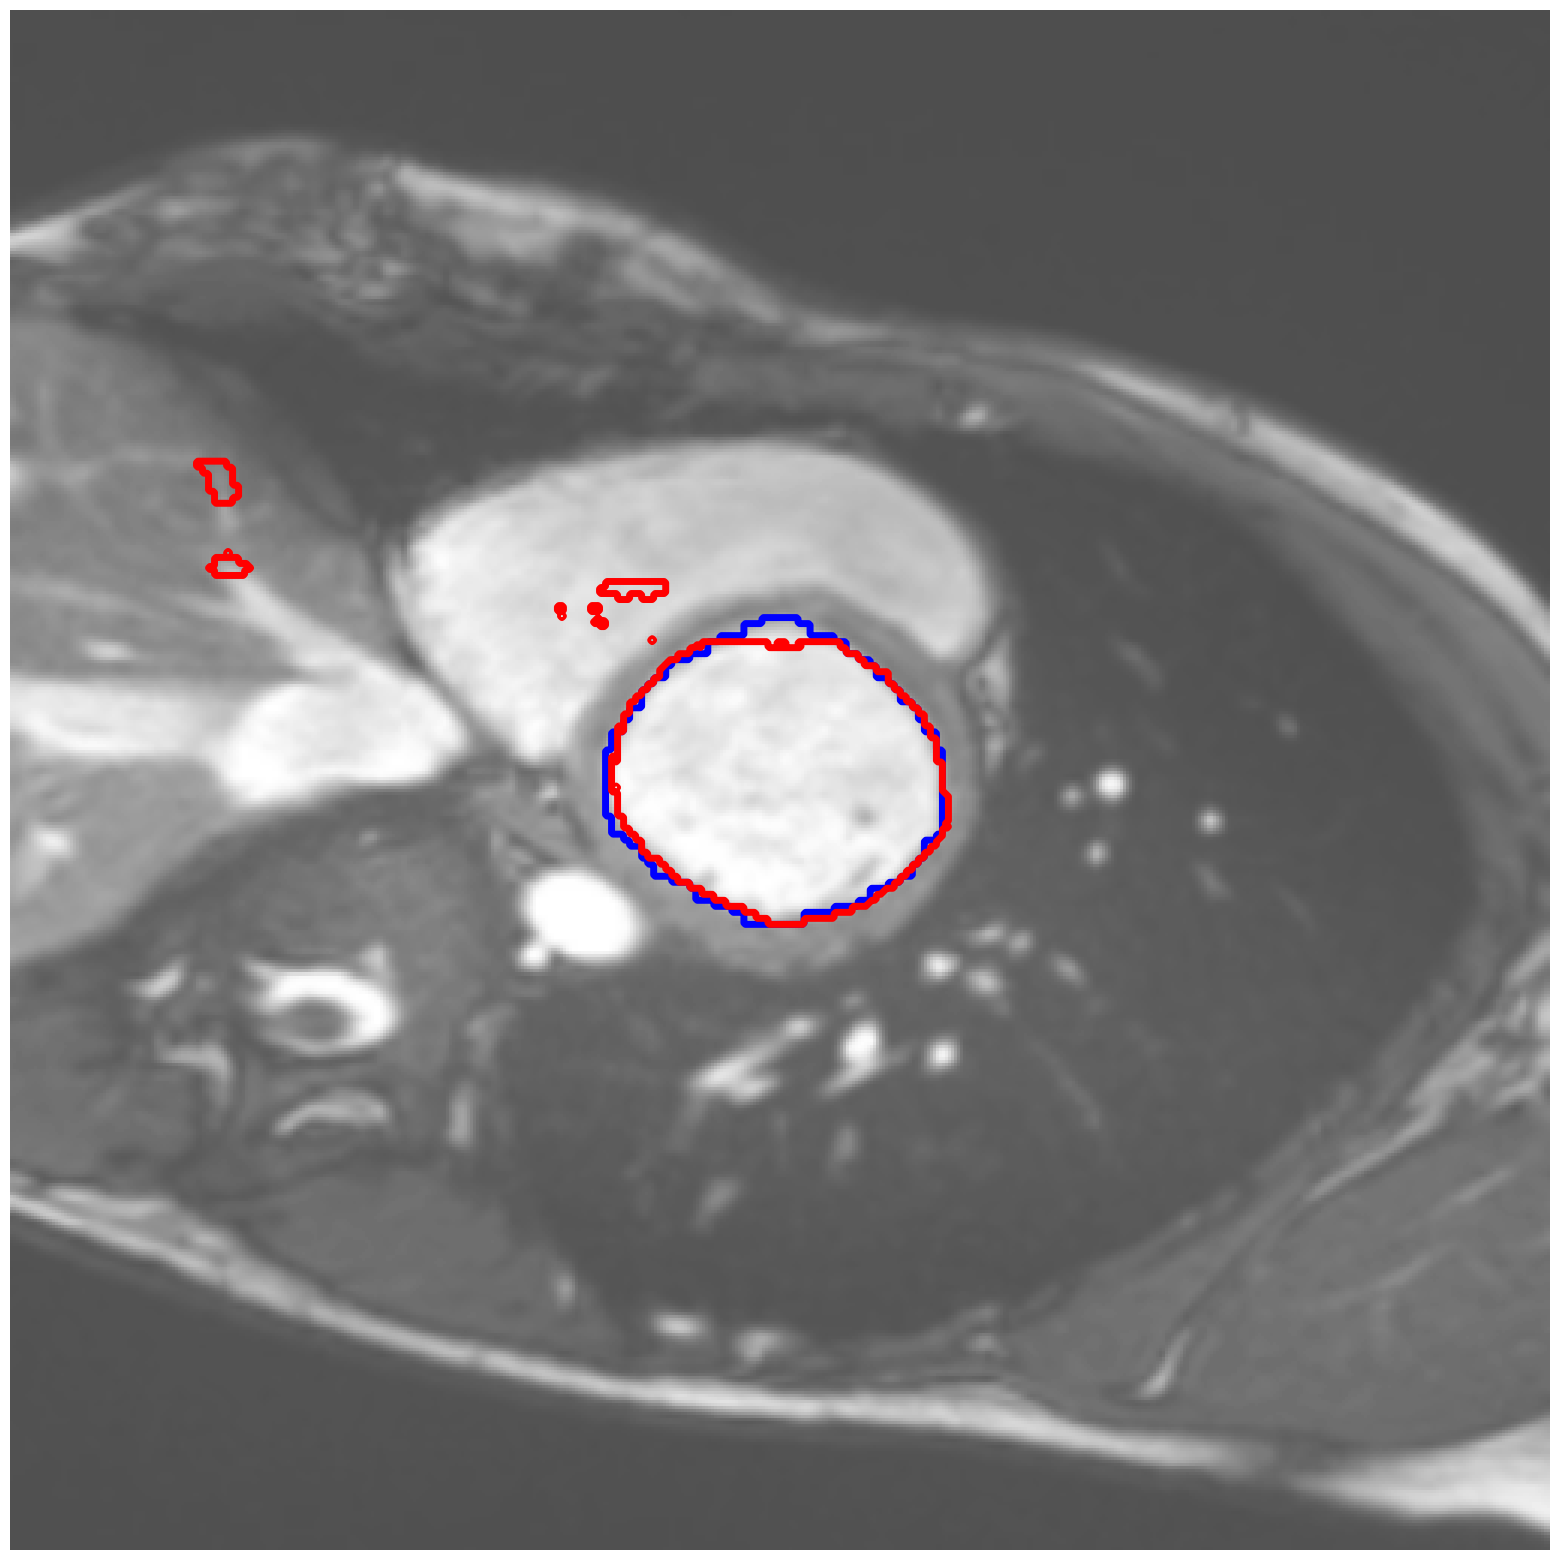

|

ACDC-RV |

![]() |

ACDC-LV |

| (a) Original pred. | b) Consema | ——— c) Standard CRC ——— | ——— d) RW-CP (Ours) ——— | |||

Visually, we observe in Fig. 1 that RW-CP is able to produce prediction sets much closer to the ground-truth than standard CRC or Consema. Our approach is even able to remove small over-segmentated areas, whereas methods such as Consema can only increase the size of the prediction set, even when the segmentation model produced false positives.

We hypothesize that the performance of RW-CP stems from its pre-processing step on probabilities, which mitigates the overconfidence commonly observed in deep learning segmentation models [16]. Their raw softmax probabilities are often skewed towards either 0 or 1 (see Fig. 1.c). This overconfidence compresses the effective range of possible values for the empirical threshold used in Conformal Risk Control, making the final prediction mask extremely sensitive to small fluctuations in . On the contrary, by first applying a diffusion process, the pixel-wise probabilities become more varied and less polarized (as shown in Fig. 1.d). This broadened distribution stabilizes the empirical during calibration, leading to a more robust and tighter prediction set, which translates to better overall segmentation metrics